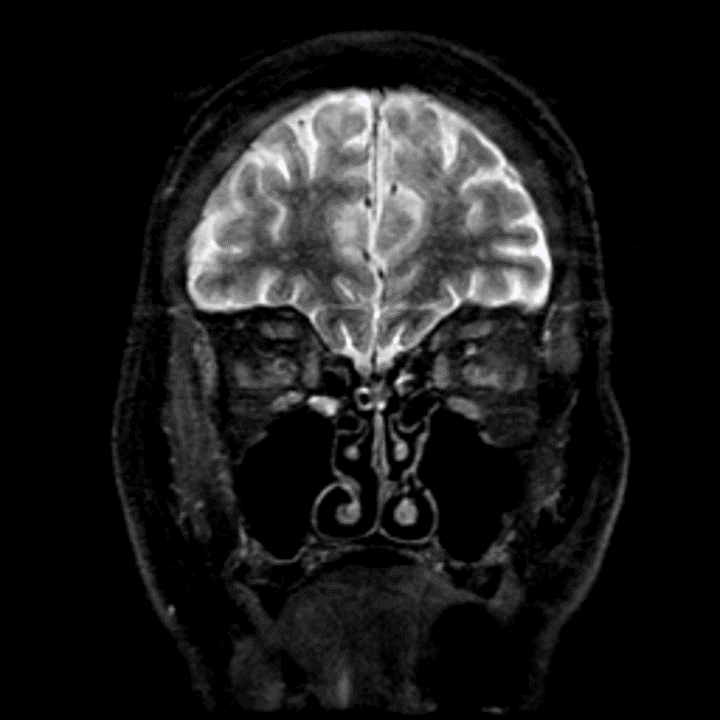

Stroke and temporal arteritis: A study of 6 cases Stroke caused by giant cell arteritis is a serious and potentially severe condition which requires a high level of suspicion and early treatment with corticosteroids. New diagnostic techniques contribute to refining patient assessment and identifying the optimal treatment.

Stroke caused by giant cell arteritis is a serious and potentially severe condition which requires a high level of suspicion and early treatment with corticosteroids. New diagnostic techniques contribute to refining patient assessment and identifying the optimal treatment. Endovascular treatment may …

Giant‑cell arteritis or temporal arteritis, the most frequent vasculitis in the elderly population is one of the uncommon causes of stroke. In the setting of giant‑cell arteritis, stroke more likely affects the vertebrobasilar territory and is the main cause of mortality.

Background: Stroke is a rare but important complication of GCA that occurs in 3–4% of patients and is typically due to stenosis of carotid and/or vertebral or basilar arteries. Despite aggressive steroid and/or immunosuppressive therapy, there is high morbidity and mortality in this patient population.